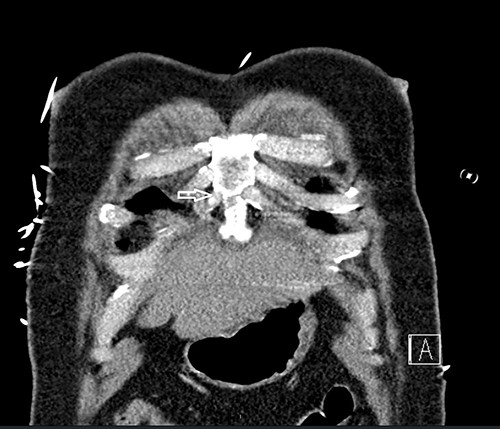

A 50-year-old 105 kg Caucasian man (BMI 32) without prior medical history presented to the trauma bay after motor vehicle accident. Physical examination in the trauma bay and computed tomography revealed fractures of right anterior ribs 2, 3, 4, 5, 6, 7 and 8, right posterior ribs 5, 6 and 8, lateral rib 9 and left anterior ribs 7 and 8, along with pulmonary contusions, left-sided hemothorax, sternal body fracture (Fig. 1) and a grade 2 liver laceration. We decided to manage the patient’s injuries nonoperatively. Under strict aseptic conditions, a thoracic epidural was placed at T5. Despite adequate pain relief from his bilateral rib fractures, significant sternal pain from the fracture persisted. Due to difficult positioning and challenges with patient cooperation, we decided to place a PIFB block as a rescue for the inadequate thoracic epidural.

Computed tomography scan showing nondisplaced sternal body fracture (arrow).